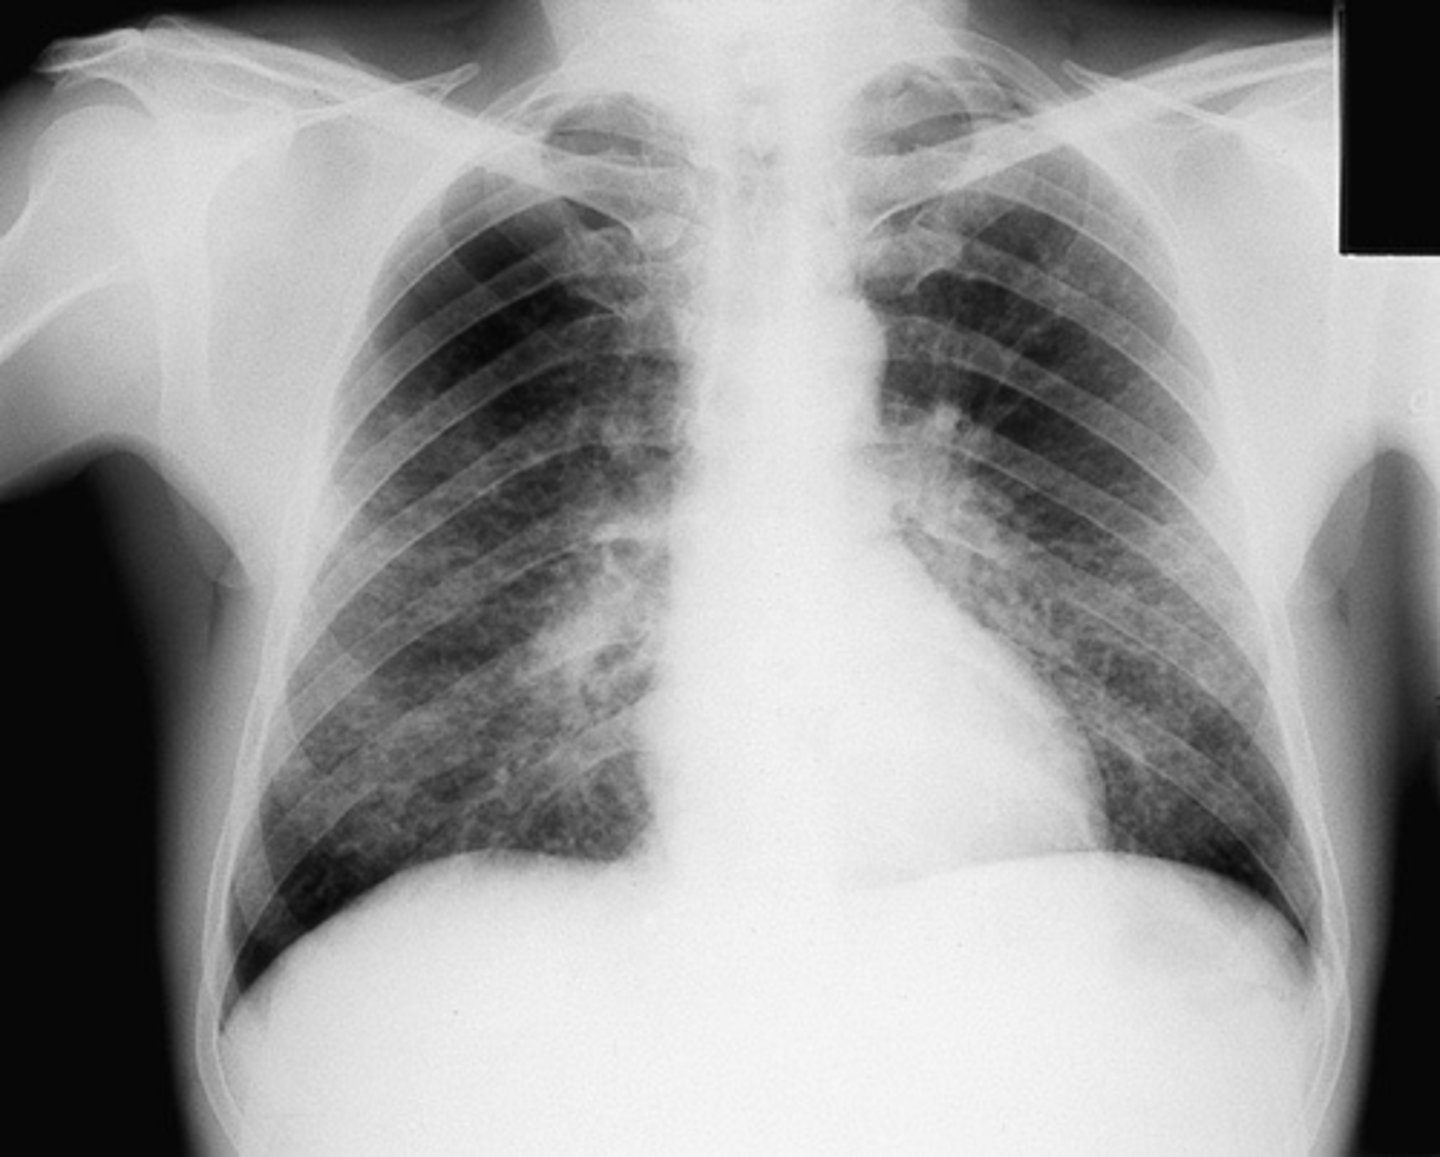

Bilateral interstitial infiltrates

Bilateral pleural effusion